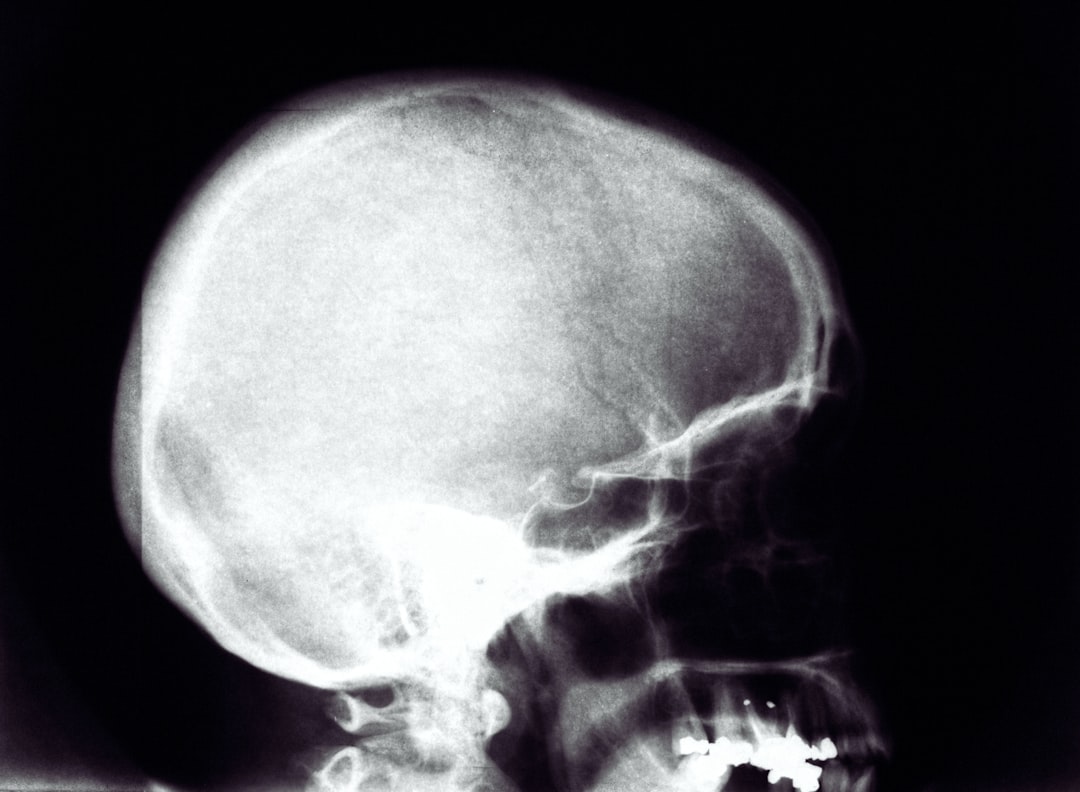

Examens radiologiques

L’imagerie médicale constitue un élément clé du diagnostic :

- Radiographie panoramique : vue d’ensemble des maxillaires permettant de localiser la lésion

- Radiographies rétroalvéolaires : images détaillées de la zone concernée

- Scanner (CBCT) : examen 3D pour évaluer précisément l’extension du kyste

- IRM : parfois nécessaire pour différencier un kyste d’autres lésions

Ces examens permettent de déterminer la taille, la localisation exacte et les rapports du kyste avec les structures anatomiques importantes (dents, nerfs, sinus).